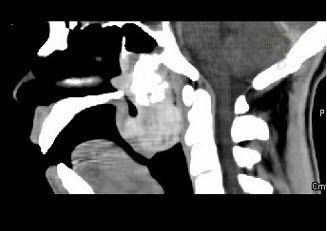

男性,57岁,睡觉打鼾,近来加重,CT扫描如图所示,请选择正确的描述和答案()。

A、鼻咽腔偏右侧可见类圆形软组织块影

B、肿块内密度尚均匀,其上方见较多钙化影

C、肿块边缘大部清楚,邻近结构未见明显受侵

D、考虑为鼻咽癌

E、考虑为鼻咽部多形性腺瘤

A,B,C,E